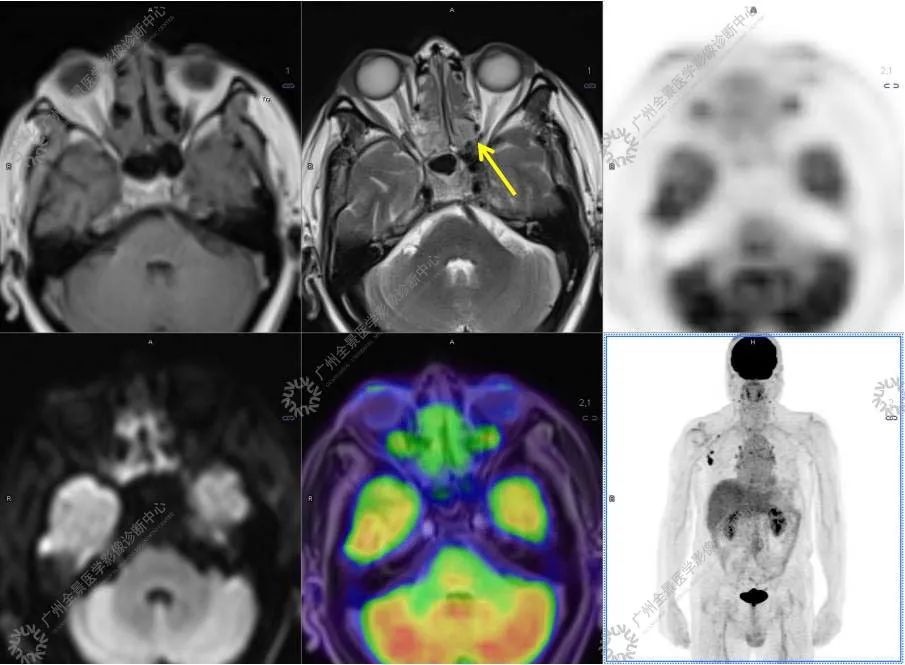

结合影像及实验室检查,临床最终考虑 IgG4 相关性疾病。

●18FDG-PET/CT 作为一种解剖和功能结合新的显像方法,IgG4-RD 的诊断及鉴别诊断中存在着巨大的优势:

●18FDG-PET/CT 扫描作为一种全身检查,有着传统影像学局部扫描无法比拟的优势,PET/CT 扫描不仅可以发现以临床症状为导向的局部病灶,更可以发现远隔部位的受累病灶。